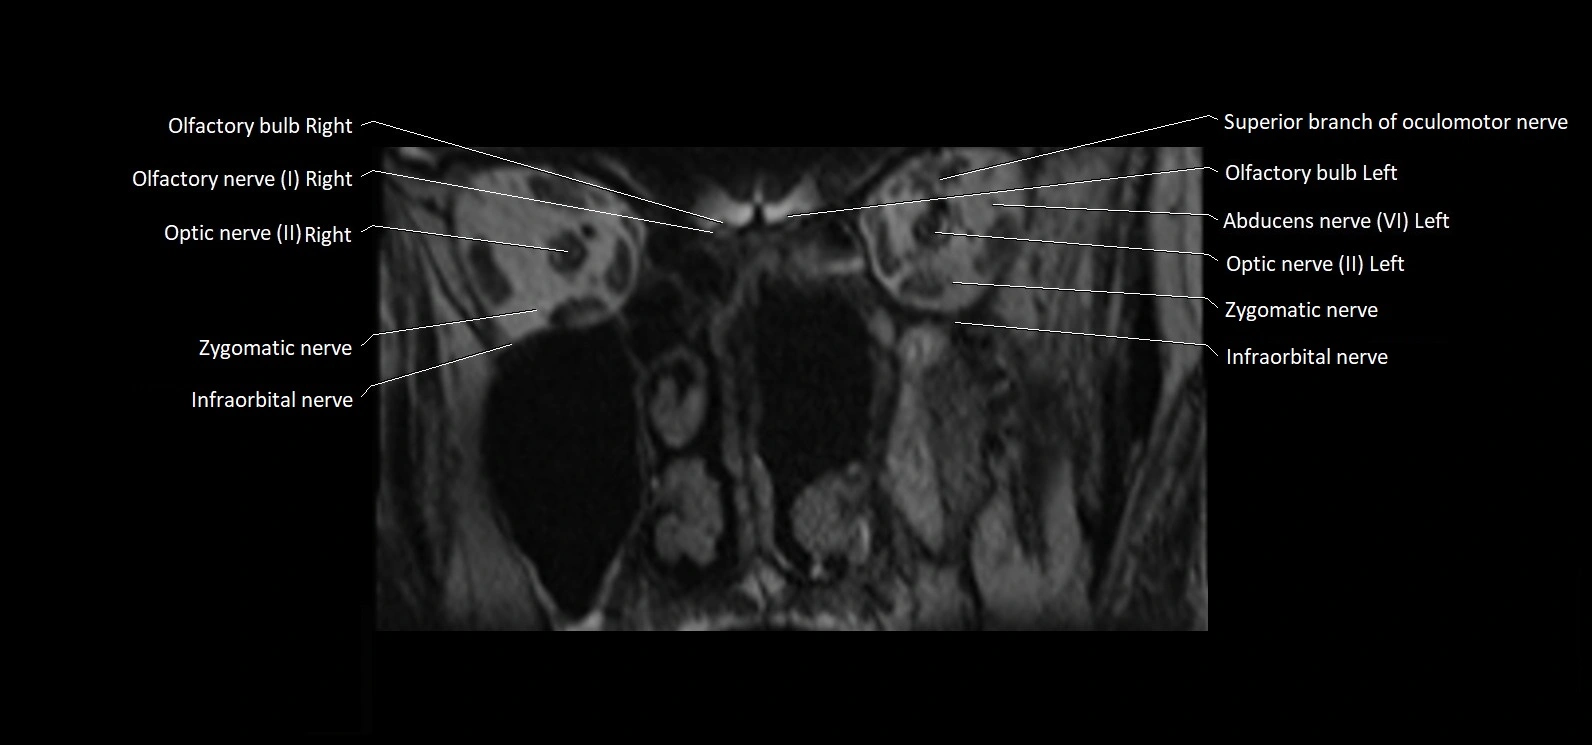

MRI Appearance

• The abducens nerve is a small, thin, linear structure

• Best visualized on high-resolution T2-weighted 3D MRI sequences (e.g., FIESTA or CISS)

• Seen as a hypointense (dark) line running from the brainstem at the pontomedullary junction, traversing the prepontine cistern, and entering Dorello’s canal under the petrosphenoidal ligament, then into the cavernous sinus, and finally the orbit

• May be challenging to visualize in standard MRI due to its small size

• Pathology may be inferred by absence, displacement, or enhancement of the nerve

MRI images

image